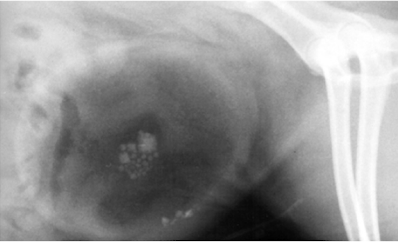

12

Q

What urolith is this an example of?

A

Calcium oxalate - irregular appearance